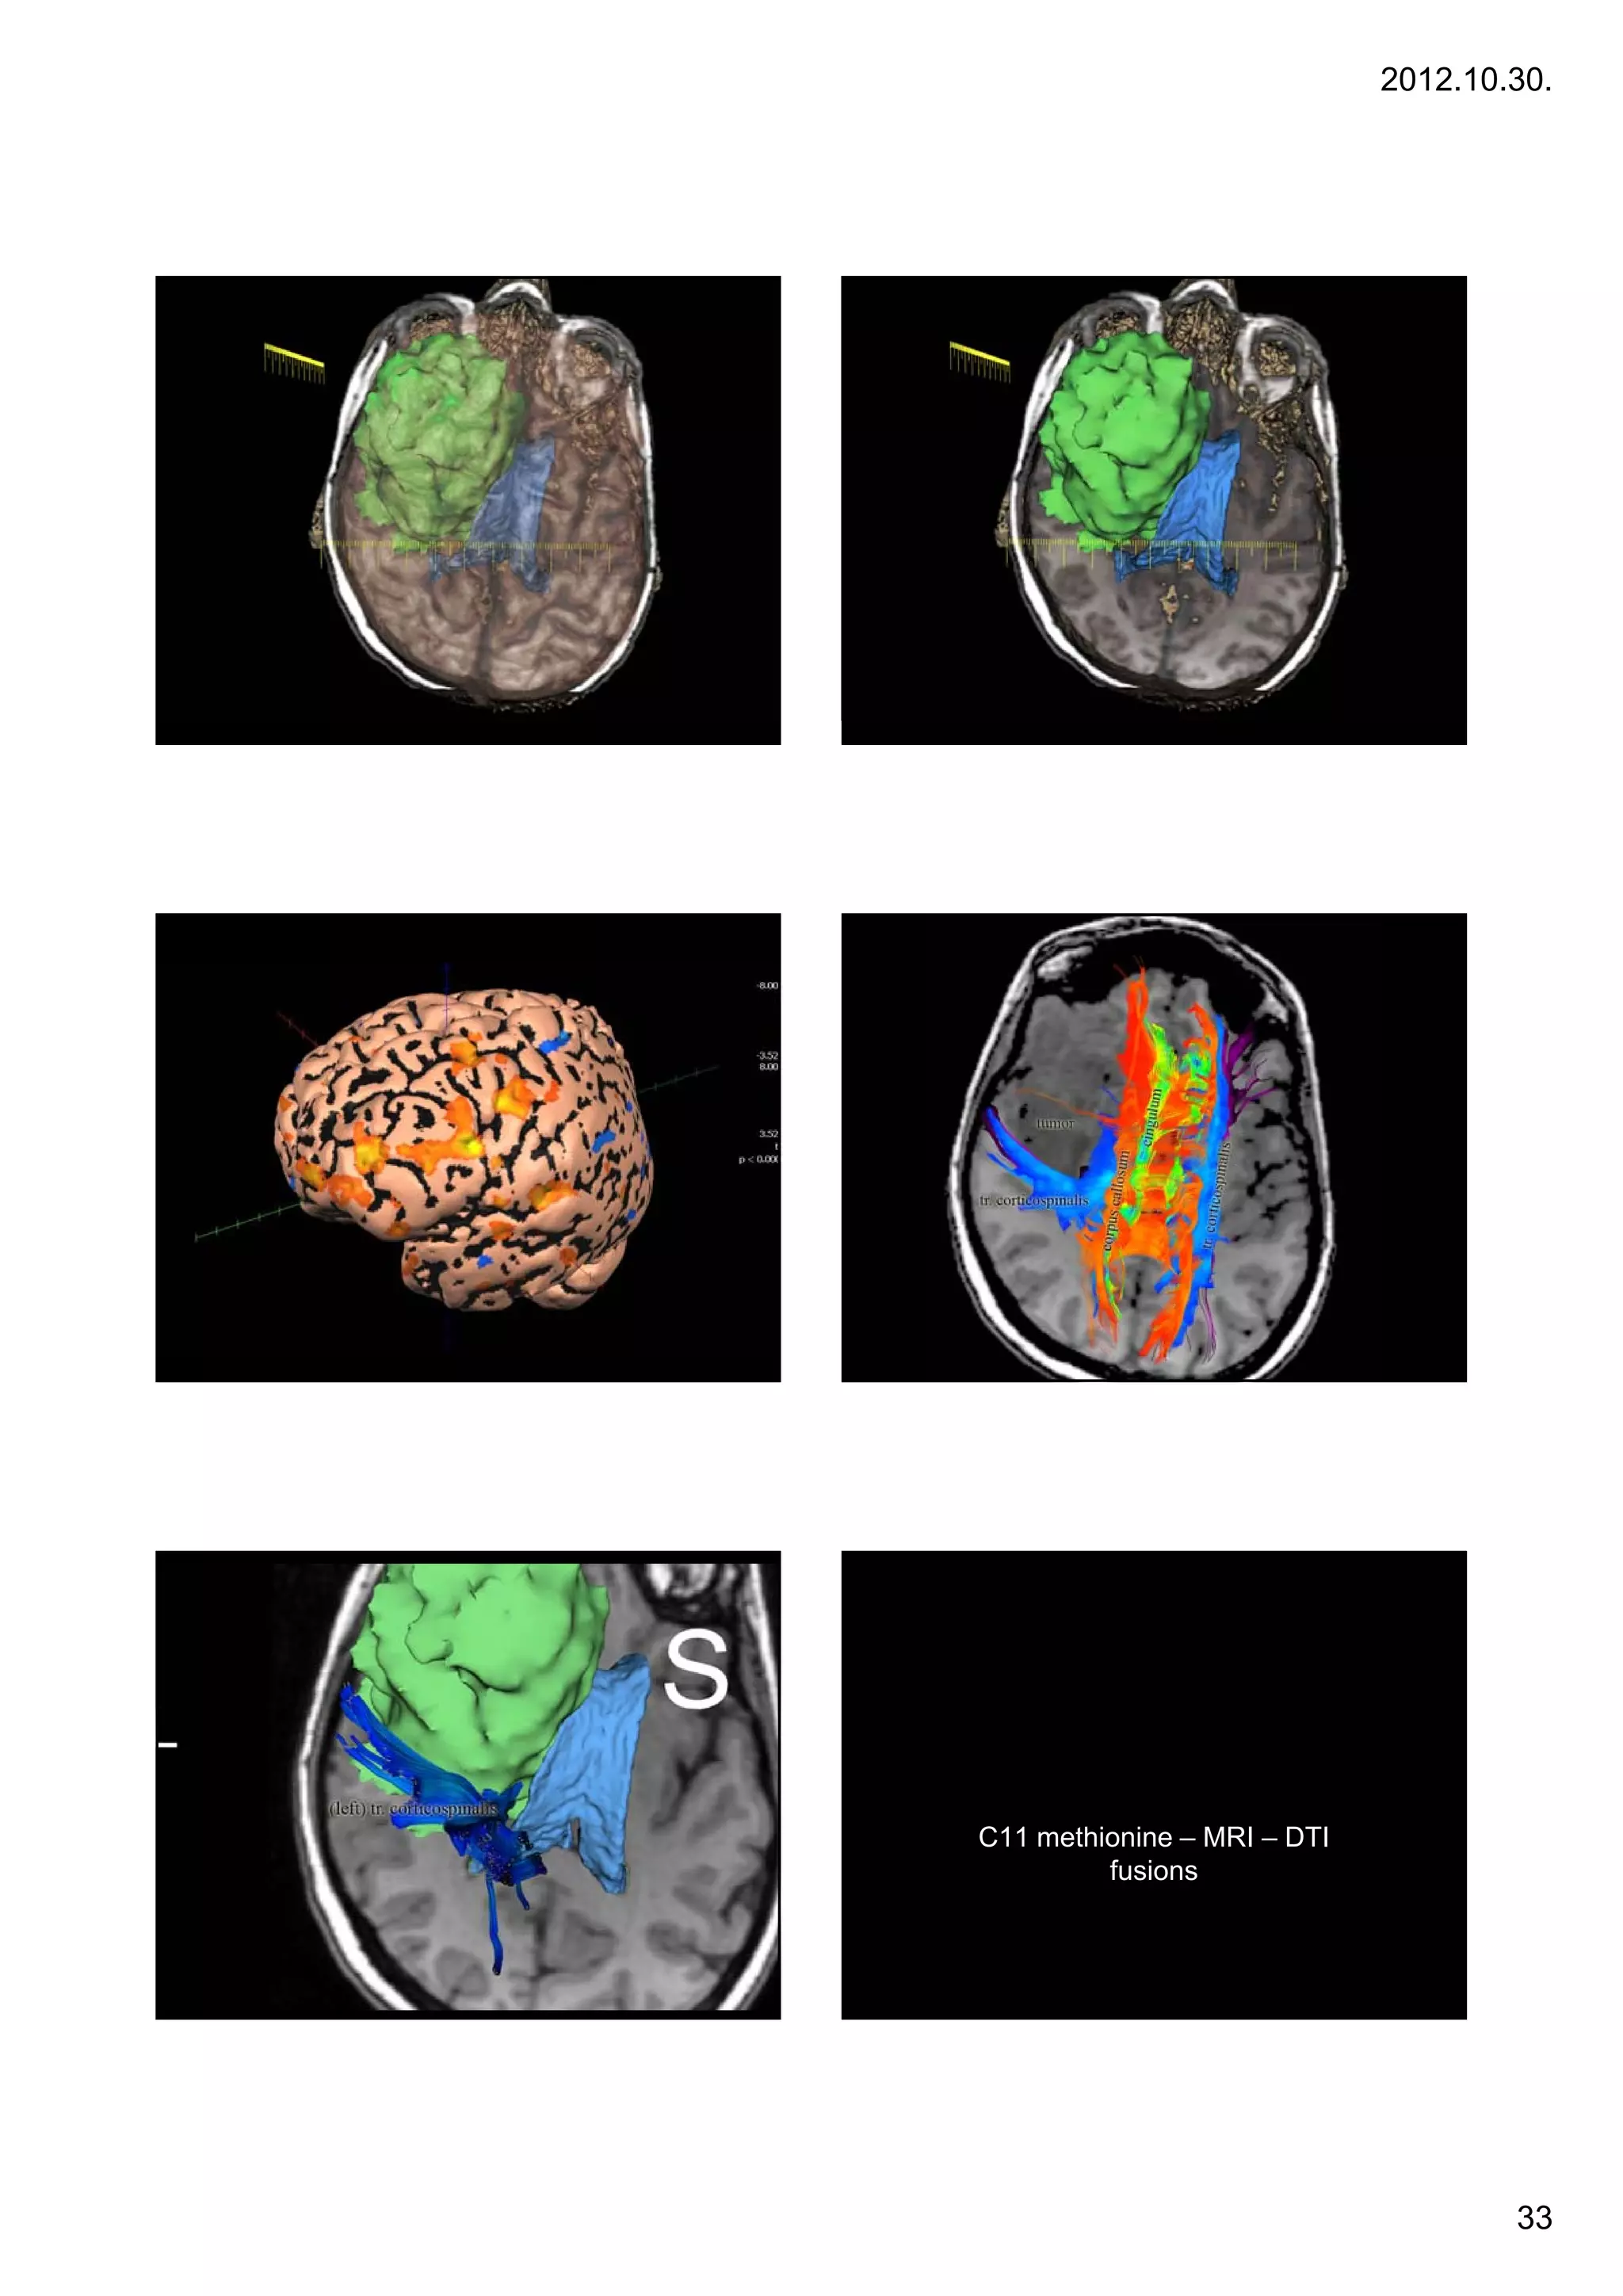

C11 methionine – MRI – DTI

fusions

• C11 – methionine

– Membrane turnover

– Cellular metabolism, tumor activity